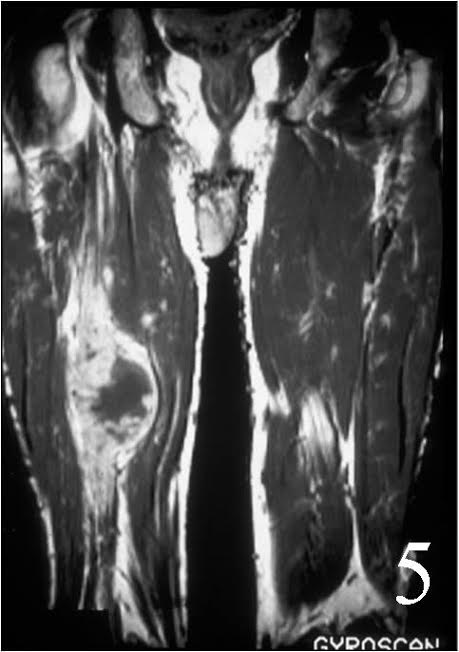

MRI of the thigh, showing a heterogeneous soft tissue lesion in the posterior compartment of the thigh on axial (Fig. 2) and coronal (Fig. 3) T1W images. The addition of gadolinium contrast shows enhancement in the periphery of the mass with necrosis and hemorrhage in the center of the mass typical of a high grade sarcoma (Fig. 4 and 5)